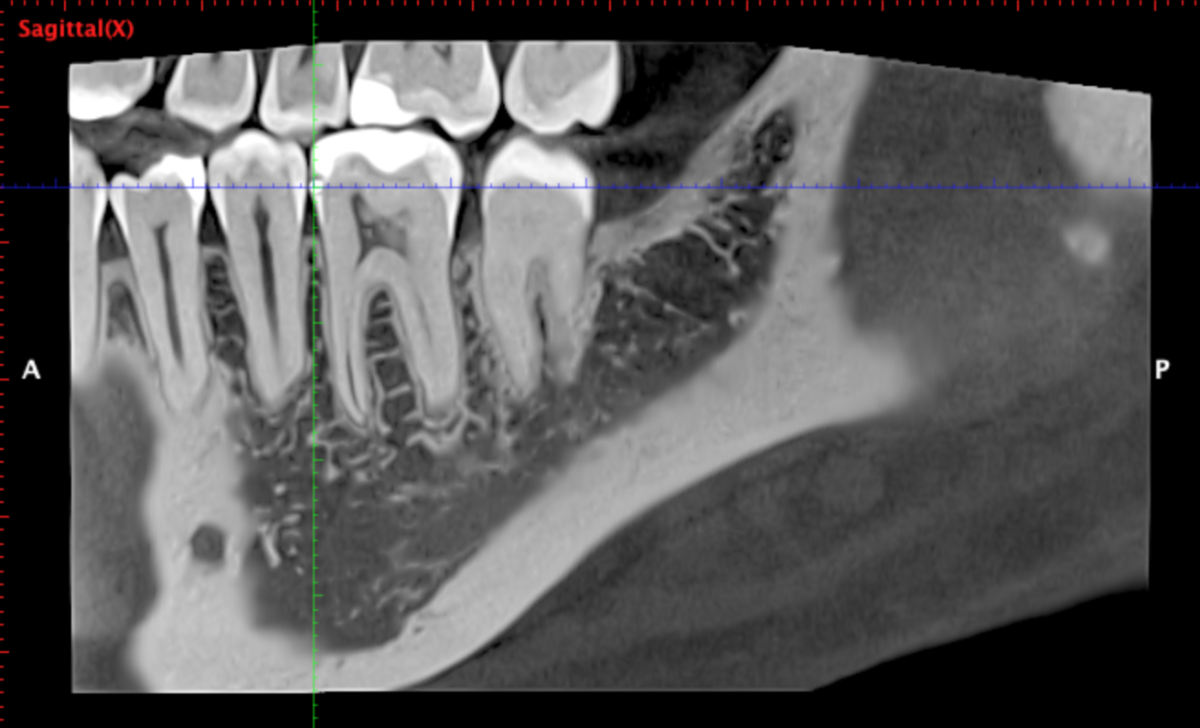

Я сделал клкт сектора 4-5-6-7 зубов справа снизу, могу приложить, если нужно. Я проходил ортодонтическое лечение, после которого у меня случилась рецессия десны на передних нижних зубах, вплоть до клыков. На самом оголоенном участке 1-2 была пластика десны пару лет назад, стало лучше. Удалены все 4 зуба мудрости